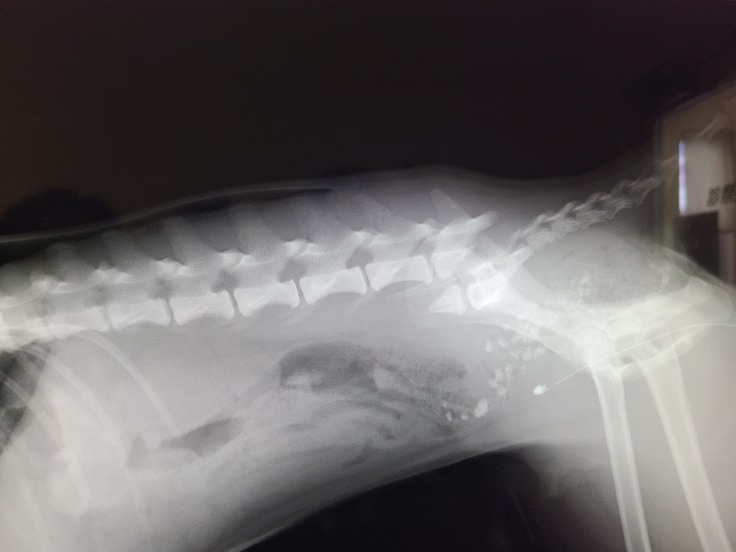

●腰椎骨折の手術

12月7日(水)、手術前日。手術の内容、万一のリスクなどの説明を受ける。

12月8日(木)、午後、腰椎骨折の手術。

画像は動物病院の掲載許可取得済

夕方、「無事、手術が終わりました。」

と病院から連絡あり。安堵。

腰椎・肋骨骨折、膀胱破裂等でそのまま入院。